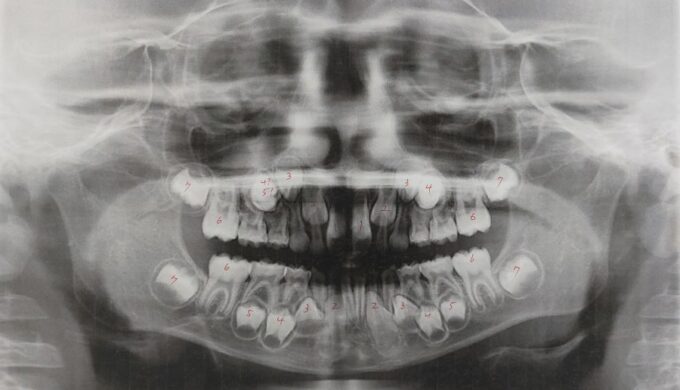

実は3年前に撮ったパノラマエックス線写真で、息子は上の5番目の歯が左右ともに欠損している「先天性欠損」と診断されました。

それが今回の過蓋咬合に影響しているかはわかりませんが、どちらにせよ歯列矯正は必要になりそうだし、ついにいくらかかるのか話を聞きに行きました。